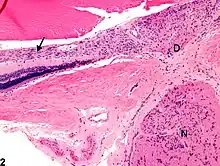

D - disco visual

N - nervio óptico